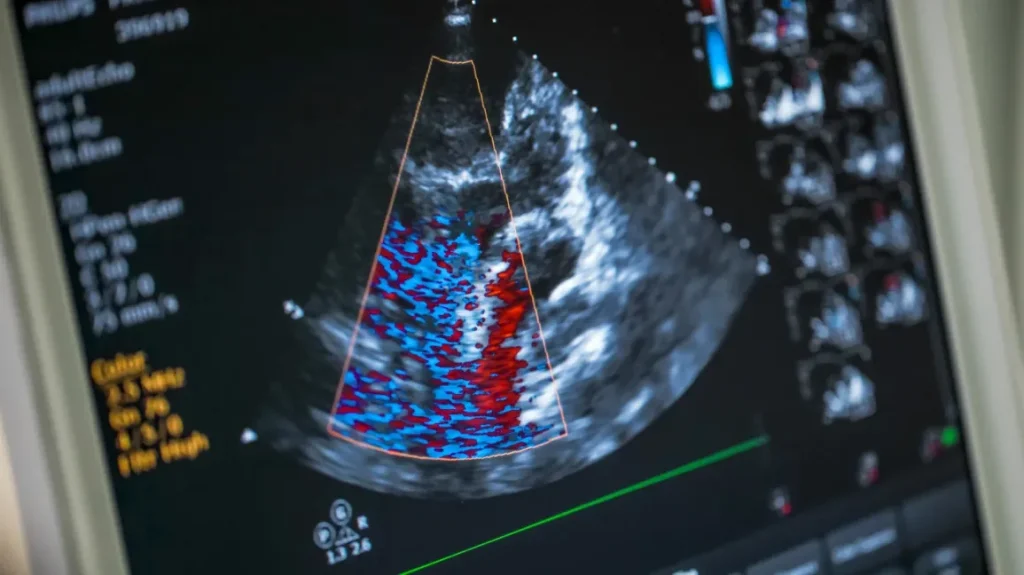

An echocardiogram checks your heart health. The test uses sound waves to create detailed pictures. When doctors review these images, they explain the findings. This knowledge empowers your decisions, so do not hesitate.

Doctors use different ultrasound methods. A transthoracic echocardiogram is standard, while an entirely non-invasive option. This test is often performed in an outpatient setting, and it usually takes less than an hour. The procedure is generally comfortable, and it does not require special preparation.

- Transthoracic Echocardiogram (TTE) provides a baseline view of your heart’s chambers, walls, and valves.